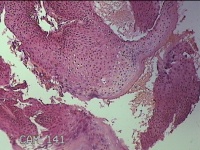

外阴赘生物

性别

女

年龄

33岁

临床诊断

外阴尖锐湿疣

一般病史

发现外阴尖锐湿疣4个月。

标本名称

大体所见

灰白暗红色不规则碎组织0.3x0.2x0.1cm一堆。

良性病变,考虑湿疣。